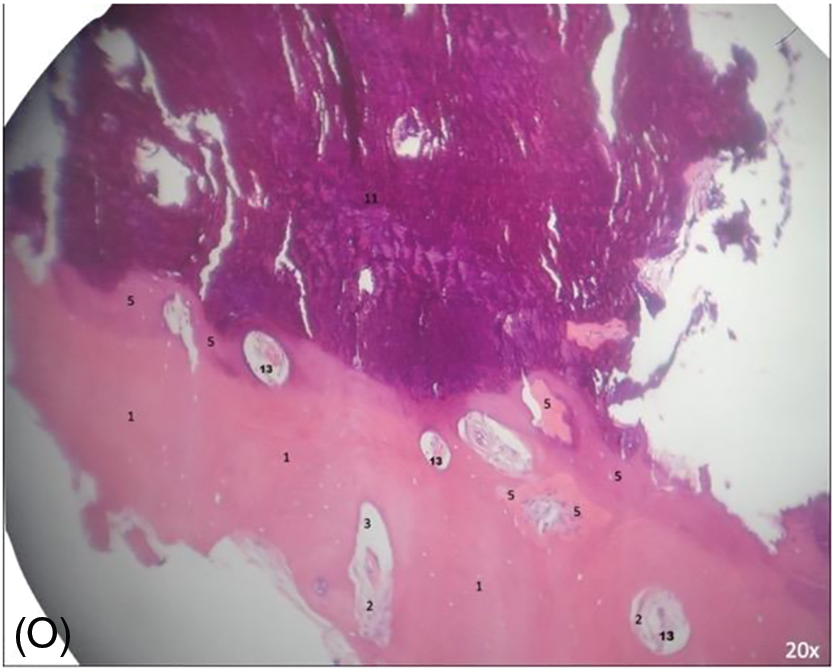

Between 5 and 12 months, the patients were recalled following the second surgical procedure for implant placement. All blocks were gently trephined in the center of the bone block using a trephine bur drill 4.0 mm ø (inner diameter) (GTD Implants). One trephine was used per patient. The pieces were kept in a 10% buffered formaldehyde solution for 48 h and subjected to descaling with Morse’s solution (pH = 4.83) for 10 days. The samples were washed in running water, dehydrated in growing ethanol solutions, clarified in xylene, embedded in paraffin, cut in the Leica LM microtome to obtain a 5 µm thickness, and collected for histological preparation. The cuts were obtained and stained in hematoxylin-eosin (HE). The material was evaluated descriptively, considering the following parameters: inflammatory reaction, connective tissue, and bone. Histological sections were observed, discussed, and described (A.P.R.S. and J.C.H.F). Digital images were acquired. This was done using an image capture system (Sony Cyber-shot DSC-W300) coupled with the Feldmann Wild Leitz 1000 light microscope (BM 2000). Images with 20× magnification were obtained.

All images were evaluated to achieve the description. The following parameters were analyzed: 1. compact (cortical) bone without osteocytes; 2. connective tissue; 3. medullar (cancellous) area; 4. osteocytes; 5. new bone formed; 6. native bone (receptor site); 7. osteoblasts; 8. trabecular bone; 9. osteoclasts; 10. osteoid matrix; 11. non-vital mineralized tissue; 12. presence of necrosis; and 13. blood vessel.

All images collected are presented in Fig. 9. The overview analysis shows that the homologous block bone graft was an osteoconductive biomaterial (Figs. 9F, 9G), with connective tissue present and newly formed bone juxtaposed on its surface. Cortical and cancellous bone, remodeling tissue, and new blood vessels were observed in all samples. The presence of vessels was the main characteristic present, which permitted the blood flow and supply for the repair/remodeling and new tissue. Newly formed bone found in Figs. 9H, 9I. Bone trabeculae with osteocytes, surrounded by connective tissue, can be observed in Fig. 9L. Active osteoblasts with connective tissue in the mineralization process and new bone were observed in Figs. 9G, 9M. The remodeling process can be found through the reverse lines, clearly seen in Fig. 9N. Foci of necrosis with fibrosis detected in Fig. 9O. Moreover, it was possible to describe areas of connective tissue with inflammatory infiltrate, but the greatest part did not have any signal of inflammation; fragments of loosely arranged connective tissue, with areas of myxoid appearance and intermingled bone trabeculae showing osteocytes, reversal lines, areas of osteogenic matrix deposition, osteoblastic paving, with few osteoclasts; peripherical and in continuity, devitalized mineralized tissue can be observed (the appearance suggests its replacement by compact bone); devitalized compact bone, with an absence of osteocytes and osteoblasts; and evidence of reabsorption.

Figure 9: (A–O) Histological analysis obtained. It is possible to observe neoangiogenesis and bone remodeling involving the bone graft used. Presence of osteoblasts and osteocytes present in the analysis. New bone formed on juxtaposition to the native bone, showing the osteoconduction principle. Number from 1 to 13 are showing specific parts found in each image (1.compact [cortical] bone without osteocytes; 2. connective tissue; 3. medullar [cancellous] area; 4. osteocytes; 5. new bone formed; 6. native bone [receptor site]; 7. osteoblasts; 8. trabecular bone; 9. osteoclasts; 10. osteoid matrix; 11. nonvital mineralized tissue; 12. presence of necrosis; and 13. blood vessel).